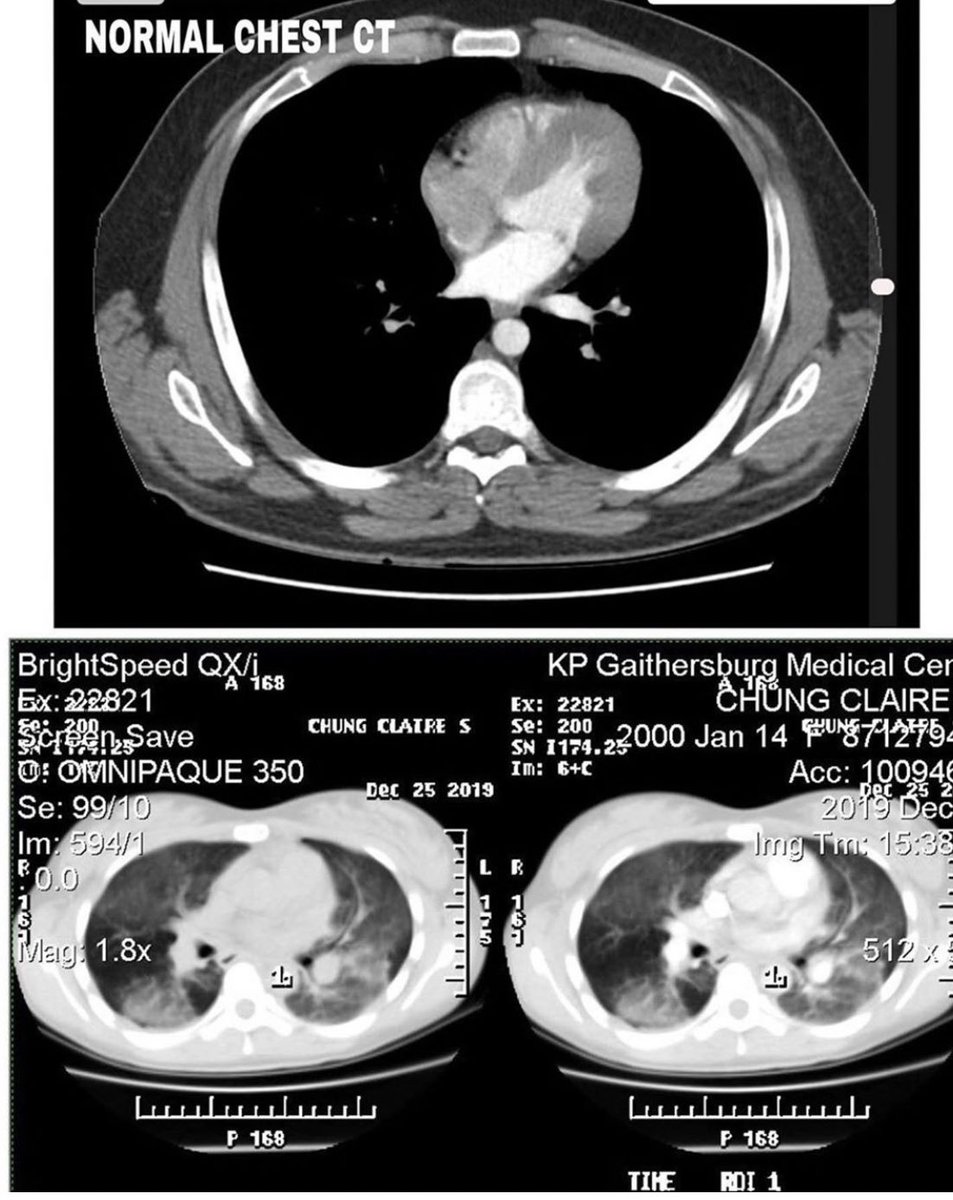

بينت الأشعة المقطعية تزايد في منطقة "الالتهاب" لتشمل الرئتين بالكامل، ولذلك تم تنويمها في العناية المركزة تحت العزل التنفسي والبدء في مضادات حيوية عن طريق الوريد

لكن النتيجة بينت تهتك وتحلل في أنسجة الرئتين مما اضطرهم للبدء بأدوية مناعية قوية عن طريق الوريد وتم وضعها على جهاز التنفس للحفاظ على حياتها حتى إشعار آخر!